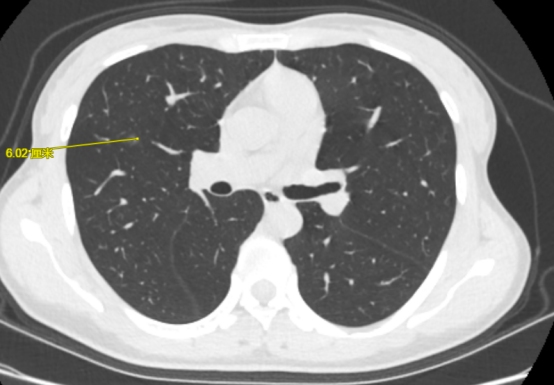

图中黄色箭头为术前模拟规划的穿刺路线

医疗组在术前的CT图像上多角度反复模拟穿刺,经过科室讨论后最终确定了理想的穿刺进针路线,为手术提供了参考方案。